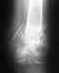

На серии МР томограмм взвешенных по Т1 и Т2 в трех проекциях с жироподавлением костных травматических изменений не определяется

Капсула сустава тонкая.

В полости сустава незначительное количество выпота.

Структура костной ткани не изменена. Локальный субхондральный склероз в области внутренних мыщелков бедренной и большеберцовой кости, шириной ~до 1.0 см.Суставная щель сужена со стороны внутренних мыщелков, конгруэнтность суставных поверхностей сохранена.Во внутреннем мениске, в заднем роге определяется патологический МР-сигнал от дегенеративного косоидущего повреждения до IIIb степени по Stoller. В переднем и заднем рогах наружного мениска признаки дегенеративноо горизонтального повреждения до II степени по Stoller.Целостность крестообразных, коллатеральных связок сохранена. Собственная связка надколенника без особенностей.

Интенсивность сигнала от костного мозга не изменена.Сигнал хрящевого компонента сустава снижен, суставной гиалиновый хрящобычной толщины, довольно равномерный.Интенсивность сигнала от клетчатки Гоффа без особенностей.Подколенная ямка не изменена.

Отмечаются заострения суставных поверхностей мыщелков, надколенника.

Окружающие мягкие ткани без видимой патологии.

Заключение: МР картина дегенеративного повреждения внутреннего (наиболее выраженно) и наружного менисков. Появления гонартроза I-II степени. Незначительные признаки синовита.